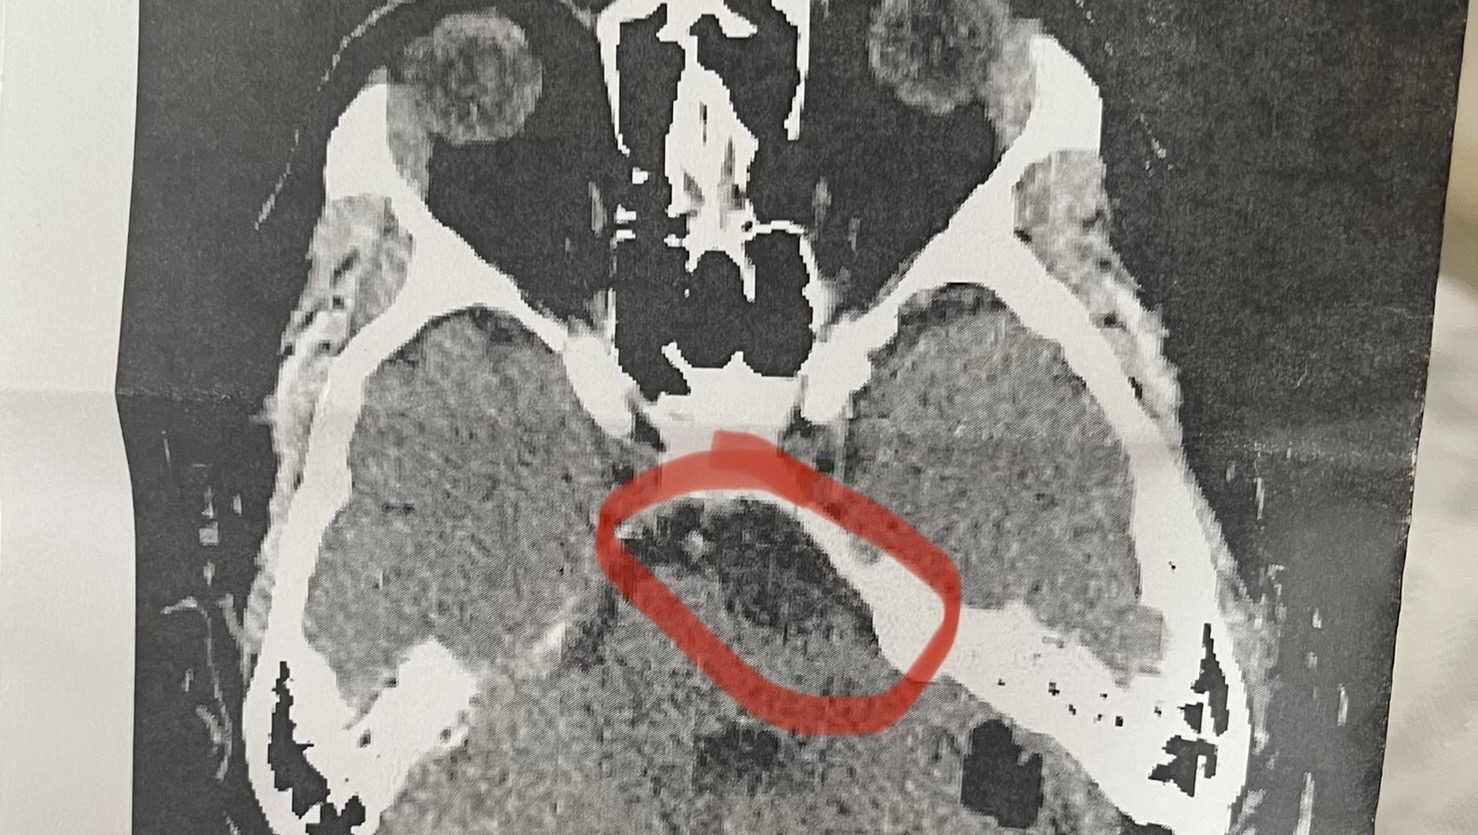

I usually talk about Haley as “Georgia’s mom” or “Adalyn’s and Emersyn’s mom” but she’s also a dear friend. She’s a fighter who has had to overcome more obstacles in her 24 years than most people do in a lifetime. Sadly, Haley has a tumor in the middle of her brain. It’s benign (thankfully) but it continues to grow and has resulted in permanent hearing loss, vision problems, and constant migraines. The doctors say that if the tumor is not removed, she will be permanently blind or deaf within a year and will steadily endure worsening physical and mental impairment.

Because of the debilitating tumor, Haley is headed into her third brain surgery. The family was able to budget and stay afloat for the previous surgery in April, but the doctors found unforeseen complications, requiring another brain surgery as quickly as possible. At the end of June, Hailey will have an even more invasive surgery with a recovery period that will include physical therapy to re-learn basic motor skills, like walking. Not only was this additional surgery unexpected, but the recovery journey will also be profoundly difficult and scary. As an additional hardship, they are also facing unexpected out of pocket medical bills.